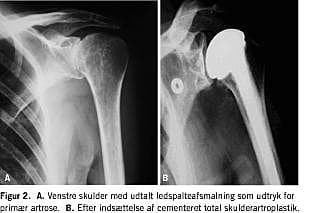

Ved degenerative forandringer af cavitas glenoidales indsættes der ofte en totalprotese, hvor der suppleres med en glenoidkomponent, der fikseres med skruer eller cement (Figur 2 ).

Resultatet efter skulderartroplastik på grund af artrose og andre degenerative lidelser i skulderleddet er i de fleste tilfælde ganske tilfredsstillende. I en prospektiv multicenterundersøgelse af 176 skulderartroplastikker indsat på grund af primær artrose fandt Norris & Iannotti [12] således, at 95% af patienterne havde opnået god eller excellent smertefrihed, bedret skulderfunktion og udtrykte en høj grad af patienttilfredshed. Tilsvarende resultater blev funder af Godenèche et al [13] i deres multicenterundersøgelse af 268 konsekutive proteser indsat på grund af primær artrose og af Fehringer et al [14].